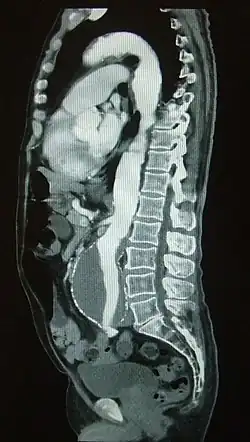

![]() Seguimiento de un bolo de contraste en su paso por la arteria aorta evidenciándose un aneurisma aórtico | ||

La angiografía por tomografía computarizada o angiotomografía es una variante de la tomografía computarizada que utiliza una técnica de angiografía para visualizar el flujo de los vasos arteriales y venosos en el cuerpo,[1] desde los circuitos circulatorios del cerebro hasta la irrigación de los pulmones, riñones, brazos y piernas.

En la angiografía por TAC, el análisis se realiza simultáneamente con una inyección de medios de contraste a alta velocidad hasta que alcance el lecho arterial de interés, empleando una técnica que le hace seguimiento a la trayectoria del bolo inyectado.[1] En comparación con la angiografía por catéter, que consiste en colocar un catéter de calibre importante e inyectando a través de éste el material de contraste dentro de una gran arteria o vena, la angiografía por TAC es mucho menos invasiva y menos incómoda para el paciente. El material de contraste se inyecta en una vena periférica mediante el uso de una pequeña aguja o cánula intravenosa. Este tipo de examen se ha utilizado para examinar a un gran número de personas en busca de enfermedades arteriales.